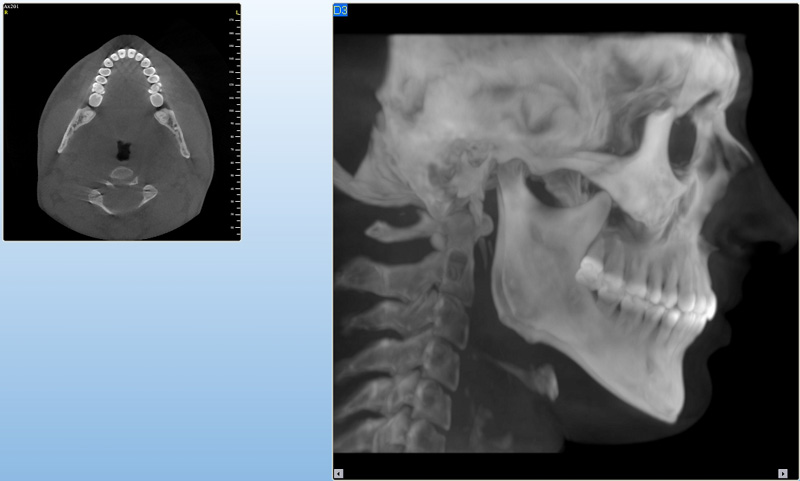

Jedná se o nejnovějším přístroj ze skupiny dentálních hybridních CBCT (3D) + 2D (pan i ceph) systémů. Přístroj umožňuje na základě jediného snímkování vytvořit všechny typy RTG zobrazení, které jsou pro lékaře potřebné.

Používaná technologii tzv. „kuželového paprsku“ a speciální senzory pro minimální zátěž při snímkování pacienta

(o více jak 80% nižší dávka proti klasickému CT).

Pomocí tohoto přístroje je možné zjisti skutečnou situaci v čelistních kostech pacienta tedy množství kosti - můžeme změřit skutečnou šířku i výšku kosti, i kvalitu kosti (hustotu) v místě uvažované implantace. 3D (tříprostorové) zobrazení umožňuje

zvýšit prostorovou představu operatéra ještě před vlastní operací a zároveň pacientovi lépe objasnit a ukázat oblast plánovaného zavedení implantátu.

Lékař si vytvoří všechny typy zobrazení potřebných pro naplánování – tedy 2D snímky (panoramatický), příčné řezy i 3D model.

Vidí zde i důležité anatomické útvary – čelistní dutinu, průběh nervu atd. Po proměření množství kosti – šířky i výšky vybere z databáze vhodný typ implantátu a umístí ho do požadované lokality.

Ihned vidí jeho pozici ve všech 3 rovinách a na všech snímcích i 3D modelu. Může upravovat podle potřeby jeho pozici, sklon atd.